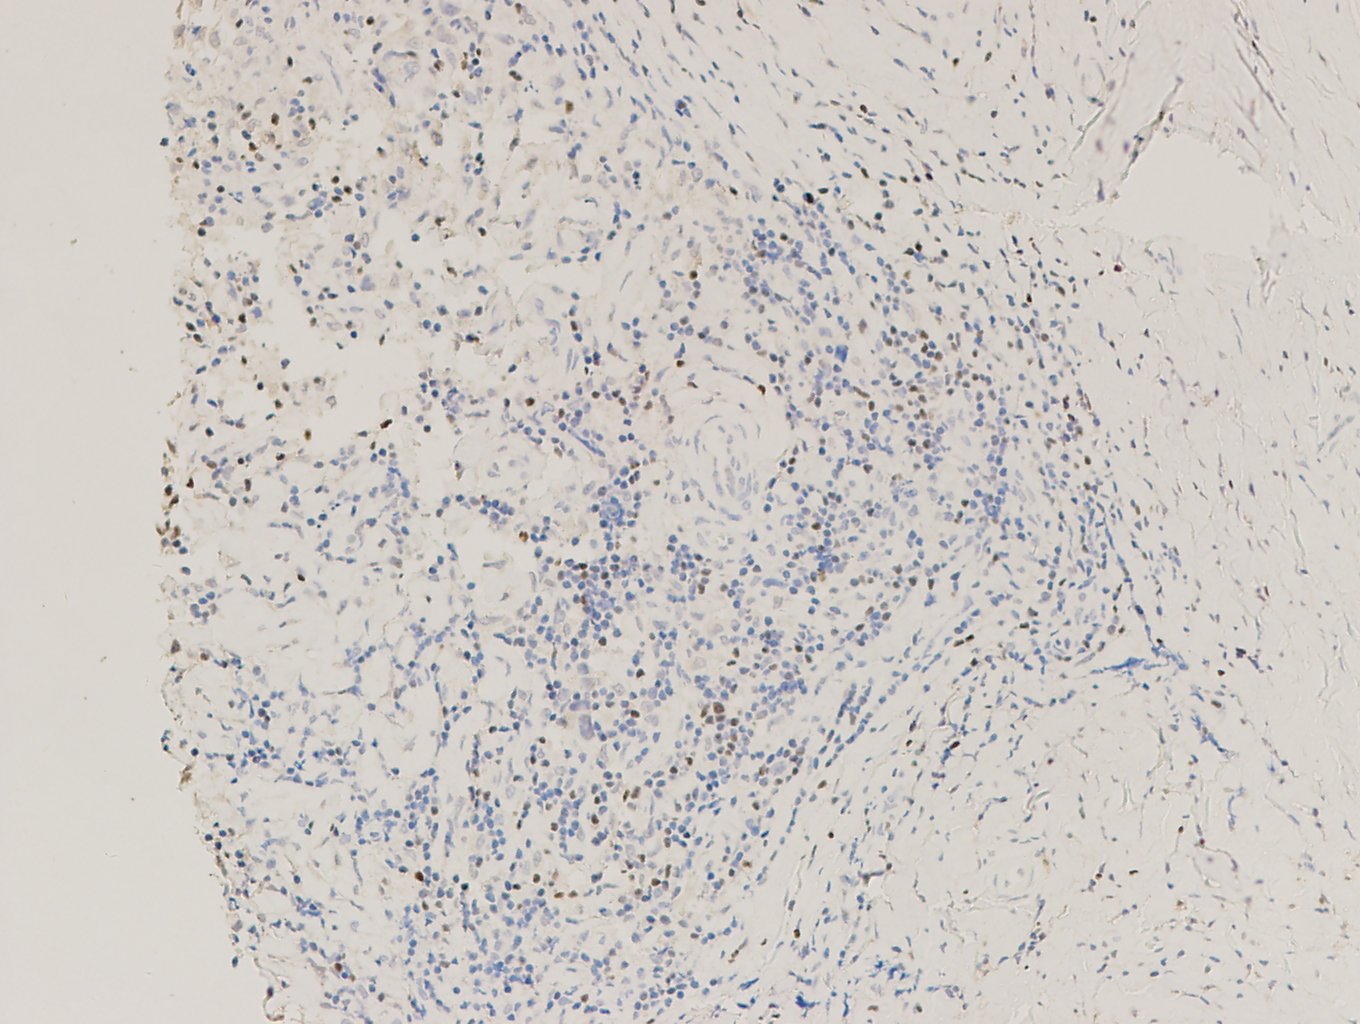

【新品單抗】FOXP3

叉頭框蛋白3(FOXP3)是Forkhead轉(zhuǎn)錄因子家族的重要成員,研究發(fā)現(xiàn)其表達(dá)于多種不同組織起源的腫瘤細(xì)胞中,并且這種表達(dá)受到多種機(jī)制的調(diào)控。

| 克隆號(hào) | 定位 | 陽(yáng)性對(duì)照 | 修復(fù)條件 |

| EP340 | 細(xì)胞核 | 淋巴瘤 | 高PH熱修復(fù) |

霍奇金淋巴瘤,F(xiàn)OXP3染色,DAB顯色